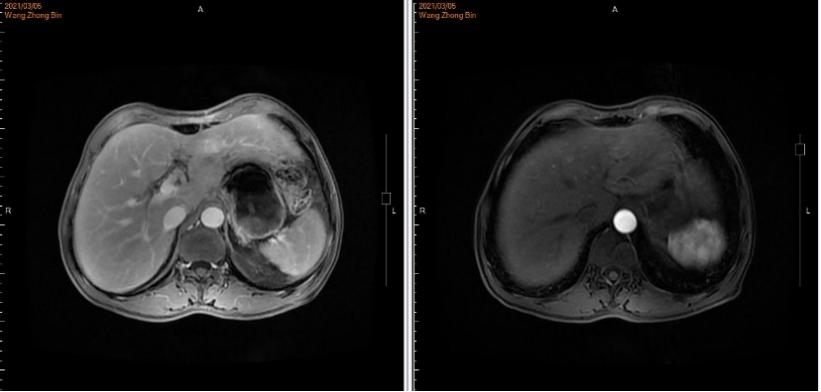

2021年3月5日术后化疗时上腹部增强MRI发现疾病进展,出现新发肝转移癌。MRI示:胃体积减小,肝脏局部体积减小,肝左叶见一类圆形轻度环形强化影,平扫显示不清,最大径约16.6mm。诊断建议:肝、胃术后改变,肝左叶环形强化影,新发肝转移。(图4)

图4. 上腹部增强MRI